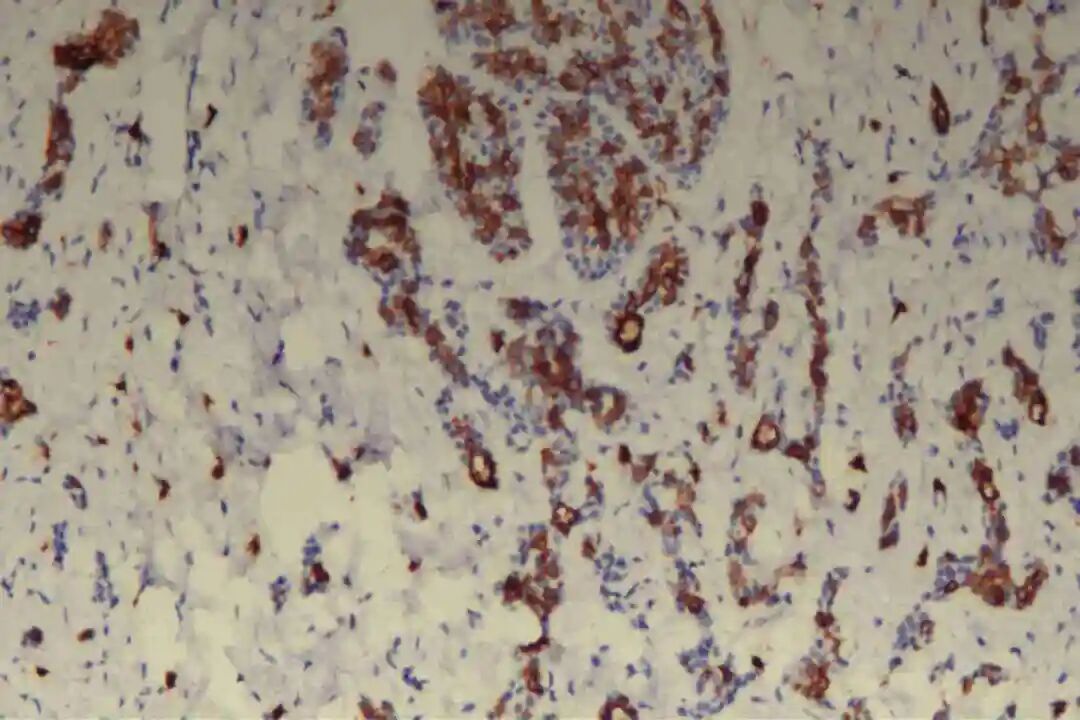

免疫组化:09号片:ER(-),PR(-),Her-2(2+),CK7(腺上皮+),CD117(+),CK5/6(肌上皮+),P63(肌上皮+),GCDFP-15(-),GATA3(-),S-100(+,显示神经侵犯),P120(膜+),E-Cadherin(膜+),P53(野生表型),Ki67(+)10%。

肌上皮细胞是PACC的重要组成部分,其标志物表达是诊断PACC的关键,主要表达p63、P40、平滑肌肌动蛋白(SMA)、肌动蛋白(Actin)及S-100蛋白,其中p63、P40呈弥漫阳性表达,SMA、S-100蛋白呈局灶或弥漫阳性表达。

此外,肿瘤细胞不表达神经内分泌标志物(CgA、Syn、CD56),可排除神经内分泌肿瘤;不表达GCDFP-15,可排除大汗腺来源肿瘤;基底膜物质(Ⅳ型胶原、laminin)阳性,主要分布于筛状结构、管状结构的腔隙周围及实性巢团的微小腔隙内,进一步支持PACC的诊断。